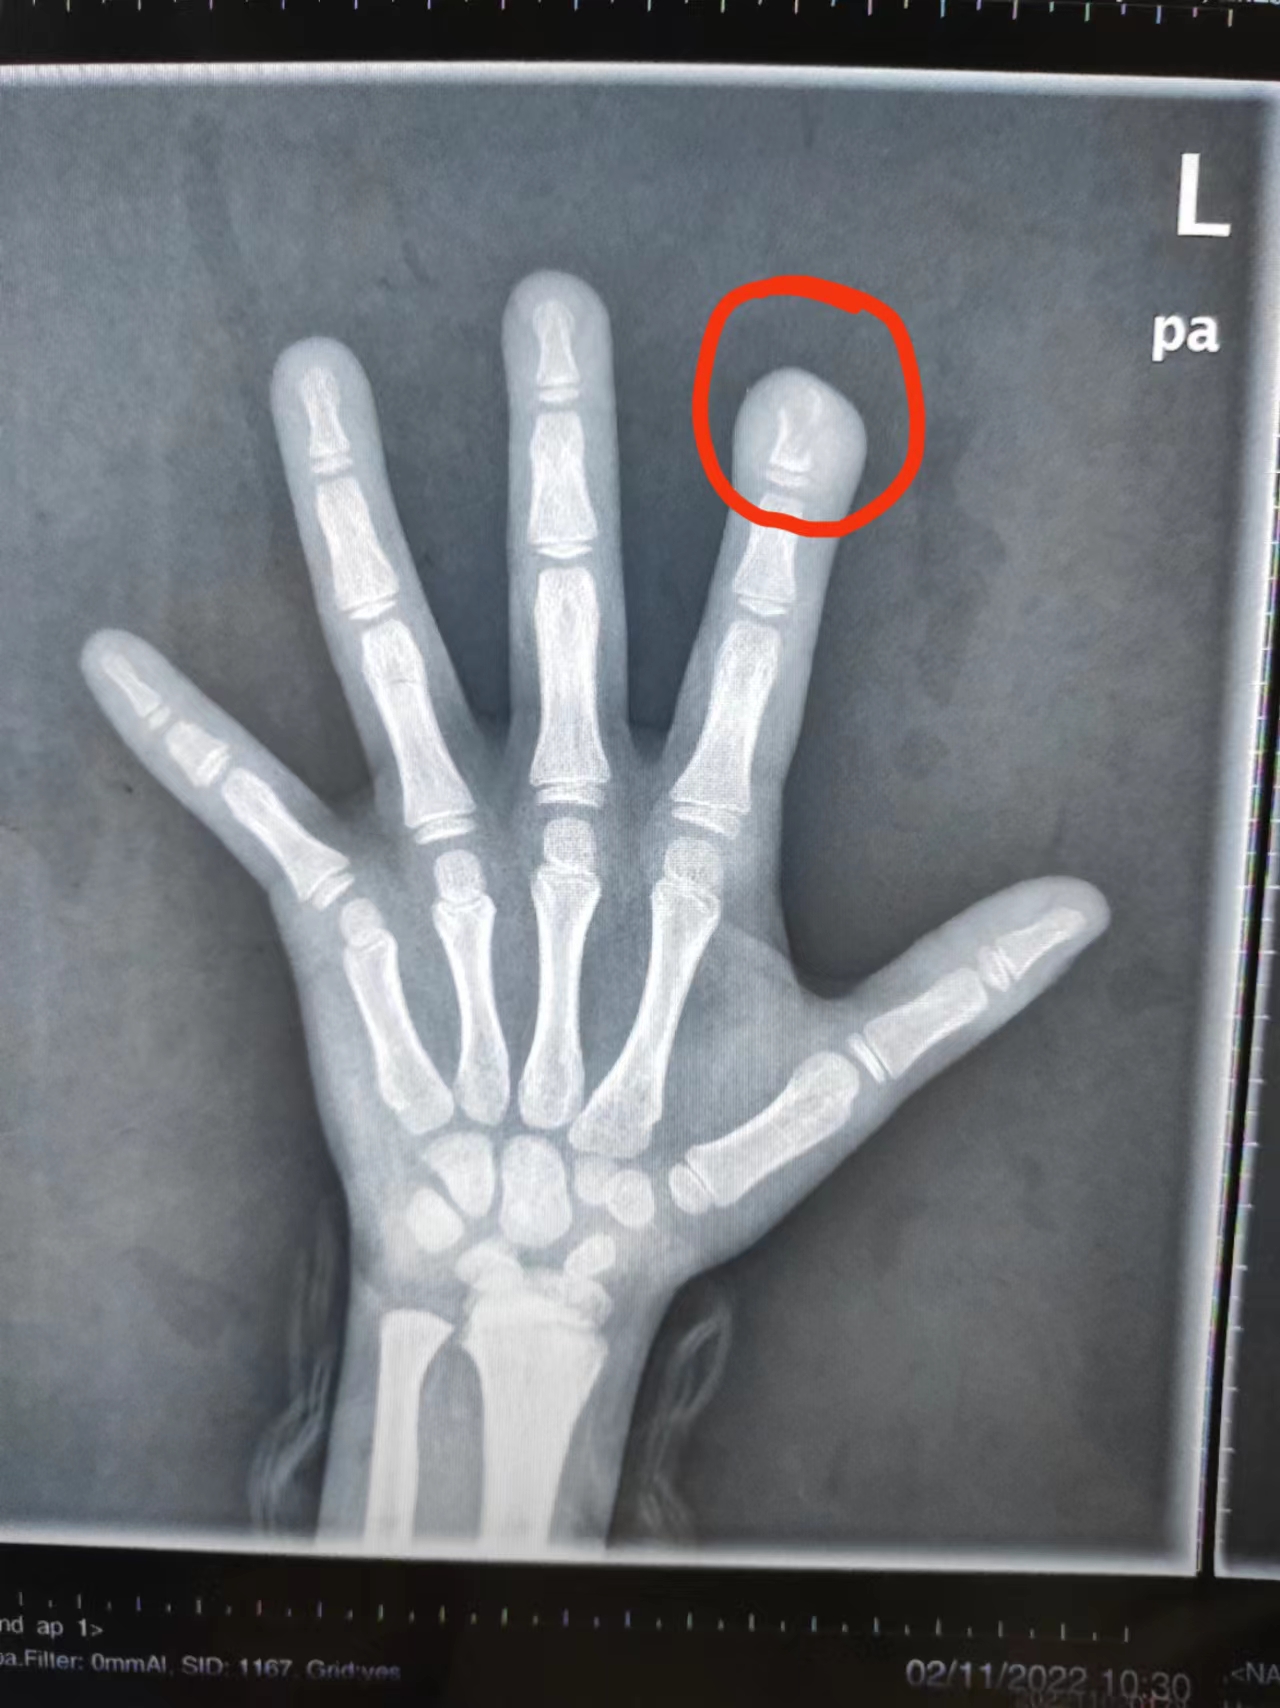

“来院时孩子左手食指指尖破溃感染,已经形成窦道,有脓性分泌物,”接诊的小儿骨科副主任医师徐剑介绍,拍片显示孩子食指指骨远节有近1厘米长的骨质破坏,已造成骨感染也就是骨髓炎,需要手术治疗。

昨天文文成功接受手术。术中看到文文左手食指指骨,如同被虫蛀过一样,医生将受到感染的骨头彻底刮掉,并用抗生素冲洗感染部位,将人工皮覆盖手指创面,在经过手术和术后治疗,文文左手食指的功能和外观将慢慢恢复正常。